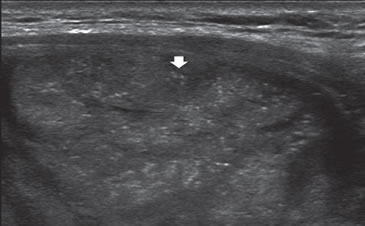

Los nódulos tiroideos se hacen palpables cuando alcanzan aproximadamente 10 mm de tamaño, dependiendo de su localización. Cuando la palpación era la principal manera de identificar nódulos, este diámetro era el límite para realizar una biopsia. Aunque las normas de la Asociación Americana de Endocrinólogos Clínicos (AACE) y la Asociación Americana de Tiroides (ATA) continúan usando 10 a 15 mm como el umbral práctico9,10 para seleccionar nódulos que necesitan de una PAAF, se ha demostrado que el tamaño no es un buen indicador para predecir malignidad. Son varios los trabajos que muestran que la prevalencia de cáncer es similar en nódulos mayores o menores de 10 mm11. La Sociedad de Radiólogos en Ultrasonido recientemente llegó al consenso de que, más que fijar un umbral de tamaño, debe usarse el aspecto ecográfico del nódulo como criterio de selección, tanto en el nódulo solitario como en la glándula multinodular4. En nódulos mayores de 10 mm no habría una diferencia significativa en el porcentaje de malignidad, aunque hay una tendencia que indicaría que la tasa de malignidad es más alta en nódulos mayores de 30-40 mm. El cáncer papilar menor de 10 mm se ha definido como microcarcinoma (Figura 1) y su frecuencia ha aumentado gradualmente en los últimos años12. Persiste el debate si este aumento es real o simplemente se debe al uso masivo de la ecografía cervical y la PAAF guiada por ecografía, lo que permite identificarlos precozmente. La presencia de múltiples nódulos no disminuye la probabilidad de cáncer tiroideo por paciente y el nódulo dominante por mayor tamaño no es necesariamente el que contiene el cáncer, ya que en aproximadamente un 30% el cáncer está en el nódulo no dominante4. Independiente del tamaño los nódulos casi completamente quísticos, sin otras características sospechosas, probablemente no requieren de biopsia.

Figura 1. Microcarcinoma de 8 mm.